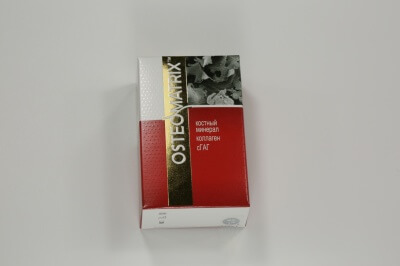

В данном кейсе автор при помощи Биоматрикса (мембрана) и Биоимплантат ГАП пошагово показывает, как спасти имплантат от развившегося периимплантита в следствии краевой резорбции.

#конектбиофарм #биоимплантгап #гап #биоматрикс #остеоматрикс #костныйминерал #bioguard #biogap #osteomatrix #костнаяпластика #нкр #резорбция #костнаярезорбция #костьизпробирки #коллагеноваямембрана #мембрана #остеокондуктор #остеоиндуктор #стоматология #статья #коллаген